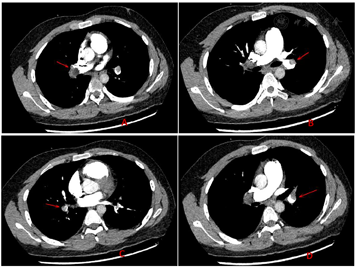

入院完善相关检查:白细胞计数12.65×109/L,血红蛋白200.00 mmol/L,肌酐125.90 µmol/L,超敏肌钙蛋白Ⅰ 2009.50 ng/L,D-二聚体57.05 mg/L FEU,全血超敏C反应蛋白35.56 mg/L。血气分析示:pH 7.48,二氧化碳分压39 mmHg,氧分压99 mmHg,实测碳酸氢根29.0 mmol/L,氧饱和度98%,乳酸1.0 mmol/L。心电图示:窦性心动过速,完全性右束支传导阻滞,V1呈qR型,V6R/S<1。心脏超声示:右室增大伴肺动脉高压,估测肺动脉收缩压为50~55 mmHg;肺部CTA示:左、右肺动脉主干、左肺上叶前段、舌段及下叶背段、前外基底段分支内见多发结节状、不规则充盈缺损影,考虑肺栓塞(图1);肺栓塞严重指数(PESI)评分:原始版本60分,Ⅰ级,简化版本1分;